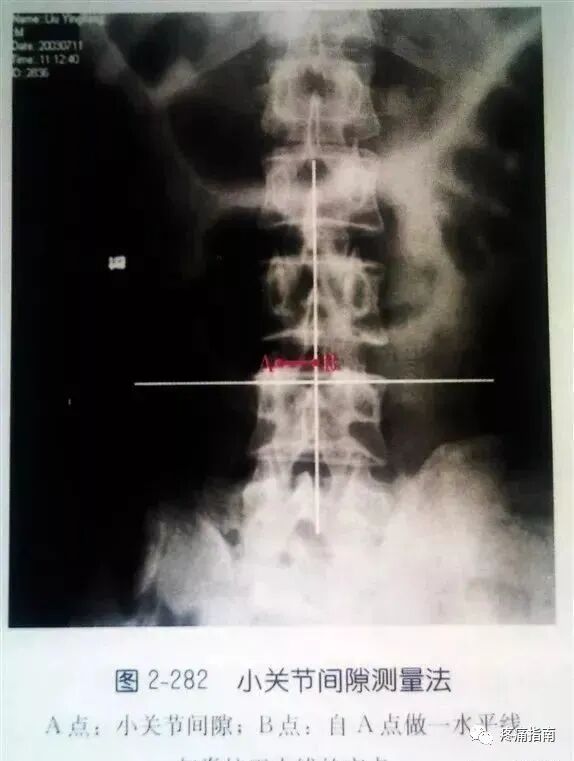

3、在腰椎正位X线平片上等比例测量带有标志线的后正中线至椎板外切迹或小关节内、外缘、小关节间隙的横向距离;由于棘突不一定完全在后正中线上,所以在后正中线上放金属标志线,测量横标志线距进针点的纵向距离。

(二)经300例病人测量的数据平均值为:

1、后正中线至小关节内缘一般在1.2-1.5cm,小关节间隙一般在1.5-2.0cm,椎板外切迹一般在1.7-2.2cm。

2、进针达侧隐窝深度,小关节内缘一般不超过5.8cm,小关节间隙一般不超过6.8cm,椎板外切迹一般不超过6.2cm。可作为临床参考。